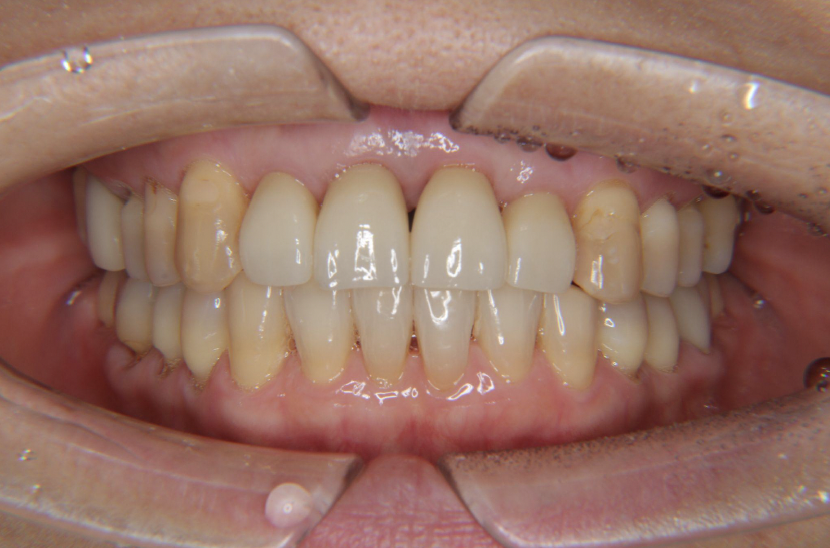

抜歯、インプラント埋入から6か月後に完成しました。

歯周病には気をつけてたつもりでしたけど、気づいたら前歯4本を抜くことに…。正直どうなるか分からなくて不安でした。見た目も心配でしたが、抜歯と同時に治療してもらえて、思ったより落ち着いて過ごせました。無事に治療が終わって、今はほっとしています。